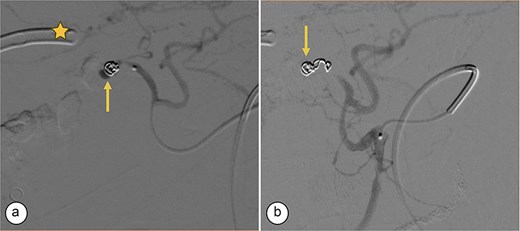

Angiography. (a) Saccular image consistent with a hepatic artery pseudoaneurysm (Segment V). (b) Pre-embolization image of the right hepatic artery showing contrast medium leakage (arrow) from a branch (Segment V) of the right hepatic artery. Right percutaneous catheter (star).

Transcatheter arterial embolization of the right hepatic artery. (a) Selective transcatheter arterial embolization (TAE) of the branch of the right hepatic artery (Segment V) (arrow). (b) Post-embolization image of the pseudoaneurysm in the branch (Segment V) of the right hepatic artery with microcoils (arrow), showing no contrast medium leakage. Right percutaneous catheter (star).